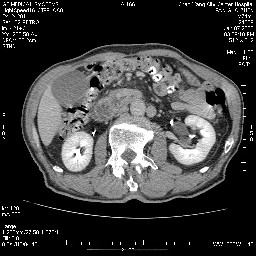

女,74岁,呕吐10余日

壶腹部的占位性病变,考虑为十二指肠癌并梗阻,但脾内多发性低密度区为转移吗?

还有胃、脾之间可见有侧支循环建立。左肾盂积水。

十二指肠水平段腔内占位伴梗阻,中等度较为均匀的强化,洗脱慢,区域淋巴结显示增多,符合腺癌表现。下腔静脉变异。

十二指肠降段扩张,水平段狭窄成鼠尾状,肠壁明显增厚,胰腺勾突增大成不均匀强化,其内可见低密度区,胆囊增大,1十二指肠水平段腺癌侵犯胰腺勾突可能大,2胰腺癌侵犯十二指肠(只有胆囊增大没有肝内外胆管扩张不好解释)代除外.

十二指肠降段扩张,水平段狭窄成鼠尾状,肠壁明显增厚,胰腺勾突增大成不均匀强化,其内可见低密度区,胆囊增大,1十二指肠水平段腺癌侵犯胰腺勾突可能大,2胰腺癌侵犯十二指肠 。

今日手术结果:胰腺钩突癌侵犯十二直肠,腹腔淋巴结转移.